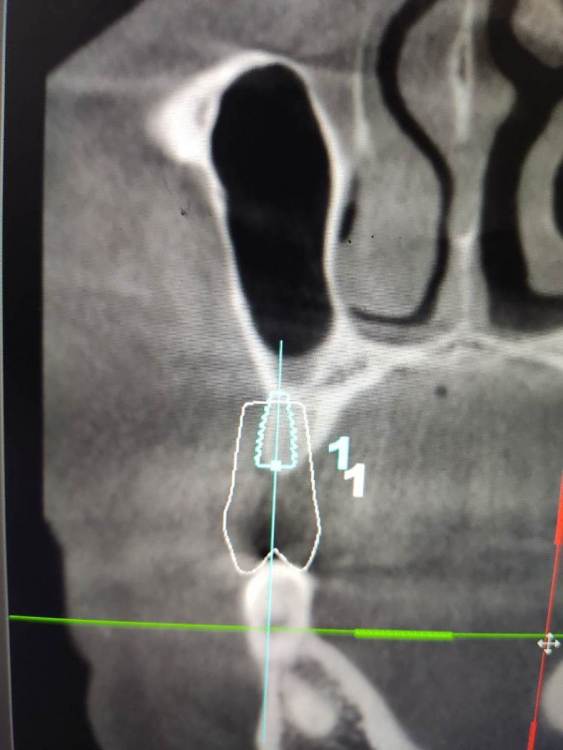

Irouil Опубликовано 4 мая, 2021 Поделиться Опубликовано 4 мая, 2021 (изменено) Тут стучать вообще не обязательно, просто пилотным сверлиться и экспандером расшириться. Если исходит из этого положения винта а если пойти ортодоксальнее и сместить его дистальнее, то ничего там при стуке не отломается Изменено 4 мая, 2021 пользователем Irouil Ссылка на комментарий

АнтонТЛТ Опубликовано 4 мая, 2021 Поделиться Опубликовано 4 мая, 2021 4.0*7.3 синус не нужен, нужна нкр Ссылка на комментарий

Irouil Опубликовано 4 мая, 2021 Поделиться Опубликовано 4 мая, 2021 (изменено) Не очень понял, что не так в предложенном автором вопроса варианте расстановки и зачем переходить на вариант с НКР и винтом 4.0? Изменено 4 мая, 2021 пользователем Irouil Ссылка на комментарий

АнтонТЛТ Опубликовано 4 мая, 2021 Поделиться Опубликовано 4 мая, 2021 Винт 4.0 потому что в данной системе, которую я поставил он 7.3мм, диаметром 3.5 только 8.5мм и более. У автора 3.6 на 7мм как я понял) Автор установил имплантат очень глубоко, чтобы избежать нкр и близко к клыка. Какой будет профиль прорезывания и что будет с костным пиком через несколько месяцев после протезирования? Ссылка на комментарий

Irouil Опубликовано 4 мая, 2021 Поделиться Опубликовано 4 мая, 2021 У меня нет дома просмотрщика с модельками, поэтому скриншотов не будет, но в целом соглашусь - нужно НКР. И вертикальный синус) Правда НКР несложная, дефект практически трехстеночный. На уровне платформы больше 3.5 мм не вижу ширину гребня Ссылка на комментарий

Женька Опубликовано 5 мая, 2021 Поделиться Опубликовано 5 мая, 2021 @АнтонТЛТ неа, 3.5*8 Можно конечно вариант который я ранее предлагал 7мм винт из которых 1.5мм полированная шейка. Но с НКР её(шейку) не совместить я так понимаю. Ссылка на комментарий